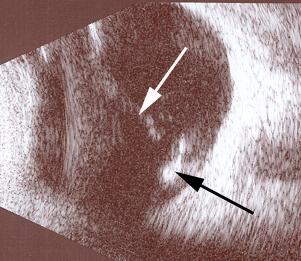

Resim 2: Yandaki resim vitreus içi kanamayı gösteren ultrasonografi görüntüsüdür. Normalde siyah olması gereken göz sıvısı (vitreus), burada opak ( beyaz ) olarak izlenmektedir ( beyaz ok).